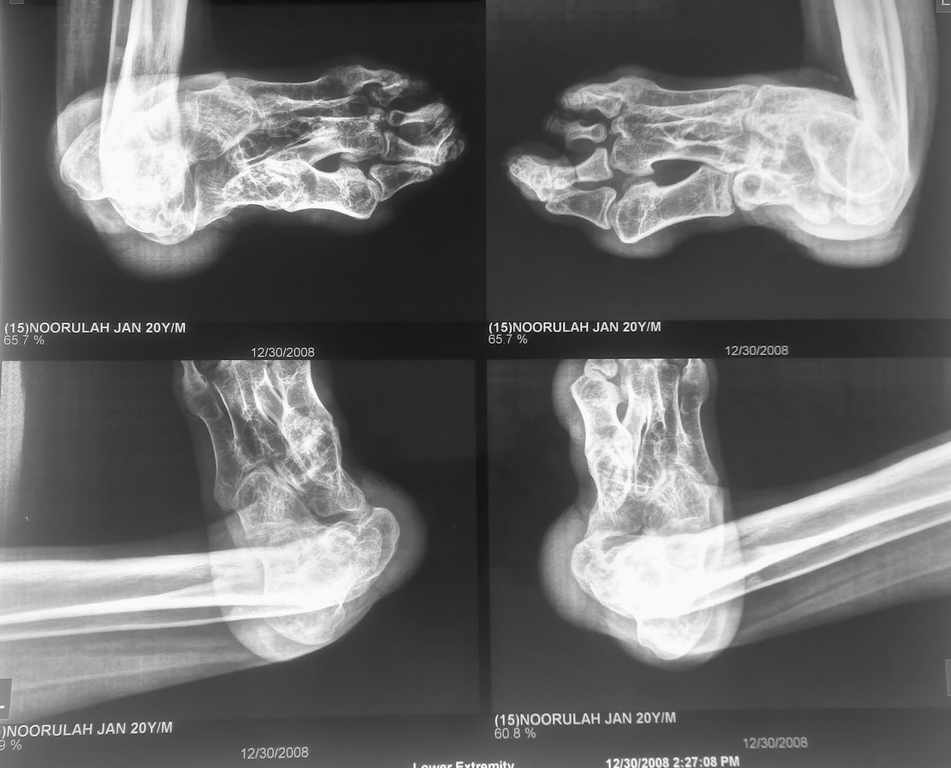

i have a patient 17 years of age, with post traumatic ankle joint dislocation,

he has walked with dislocation for 6 years now and has this

deformity,, can some body suggest what would be the appropriate name

to describe it, and treatment options